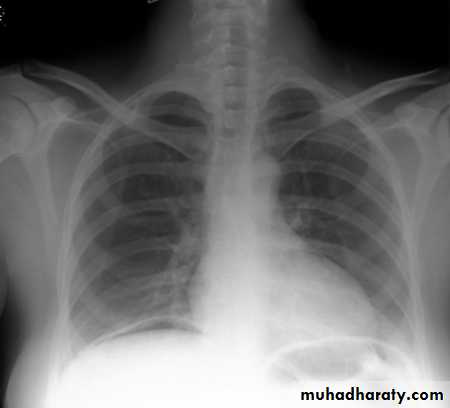

SLIDE NO. ((11))Female patient with history of asthma presented with severe dyspnoea and absence of breath sound on the left side

• What is the diagnosis?

• What immediate action you undertake?SLIDE NO. ((12)) Patient sustnained car accident. He has dyspnea, absence of breath sounds in the left side